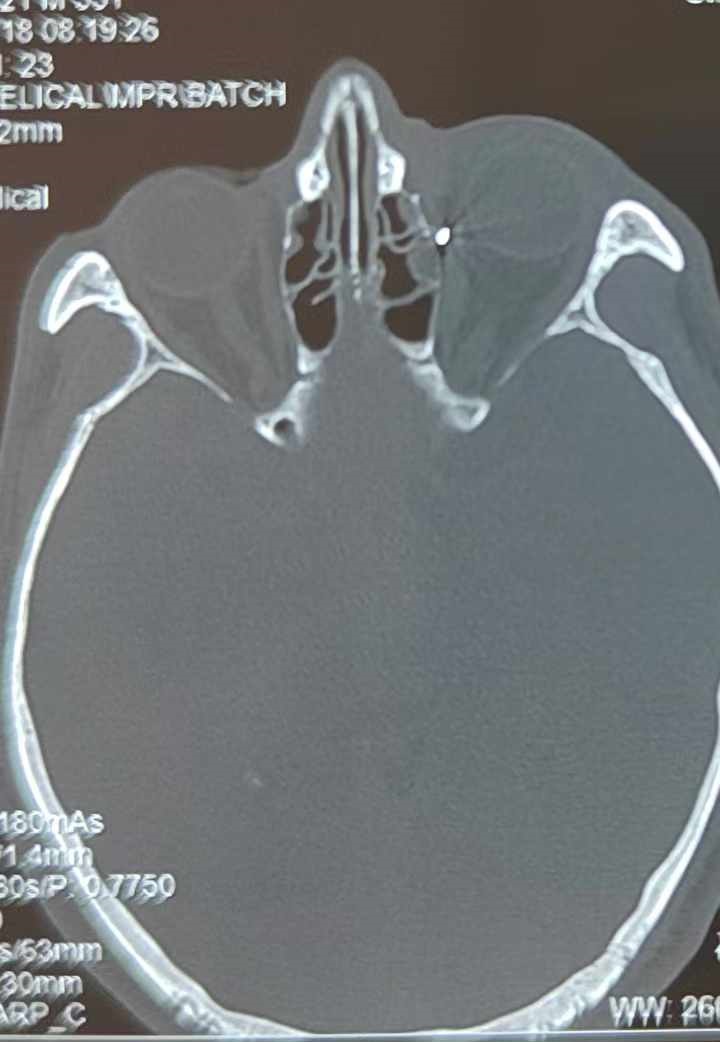

裝修工人高先生在作業(yè)過(guò)程中不慎被砸傷左眼,送至廈門眼科中心救治時(shí),眼外傷及眼底病2科副主任醫(yī)師李海波博士在CT檢查報(bào)告中發(fā)現(xiàn),進(jìn)入眼內(nèi)的異物在眶尖極為隱匿的位置,想要“不動(dòng)聲色”地取出來(lái),有些難度。

從CT報(bào)告中可以看出,高先生眼內(nèi)的異物不是很大,但位于眼窩深處,緊鄰鼻骨,從CT影像判斷應(yīng)該是金屬或合金異物。一般臨床上遇到這樣的情況,醫(yī)生會(huì)建議“保守觀察”,若異物傷及神經(jīng)、發(fā)生炎癥感染等,則需到條件較好、有眼眶病和眼外傷專業(yè)醫(yī)師的醫(yī)院進(jìn)行二期眶內(nèi)異物取出術(shù)(2021年《中國(guó)眼眶異物診斷和治療專家共識(shí)》)。

李海波博士介紹,眶內(nèi)異物想要通過(guò)手術(shù)取出,難度很大,一是因?yàn)槲恢秒[匿,無(wú)法實(shí)現(xiàn)可視化操作;二是如果是磁性異物,現(xiàn)有手術(shù)工具磁性強(qiáng)度有限,很難吸出這么深的異物;三是可操作空間極為狹小,眶周軟組織多,異物周邊包裹緊密,像高先生這種情況,異物周邊還有很多神經(jīng)、血管,手術(shù)難度更高。

手術(shù)十分順利,李海波博士設(shè)計(jì)好了取出路徑,用這根細(xì)磁棒取出了一個(gè)米粒大小的鐵屑,過(guò)程中未造成二次傷害和大創(chuàng)面?zhèn)?。術(shù)后CT檢查顯示,高先生眼內(nèi)再無(wú)異物,他此時(shí)才松了一口氣。